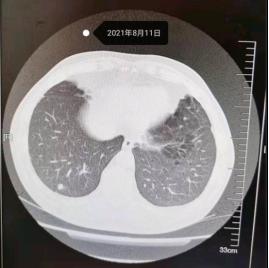

戴主任您好,我今年60岁,2021年8月11日因为慢支肺炎在齐齐哈尔住院,CT检查发现肺结节9mm,抗炎10天。

2021年8月19日做肺结节分析,直径约为9.9mm,体积约为509.6mm3,CT值约为—198HU.形态不规则,似见浅分叶,其内可见血管通入,边缘毛糙。双肺多发小结节,大部分位于胸膜下,长径2—3mm,右肺下叶结节N1,恶性病变可能。家族病史:父亲66岁,母亲46岁,均因肺部疾病去世。

看不太清楚,但确实是高危结节,有手术指征,治愈率极高